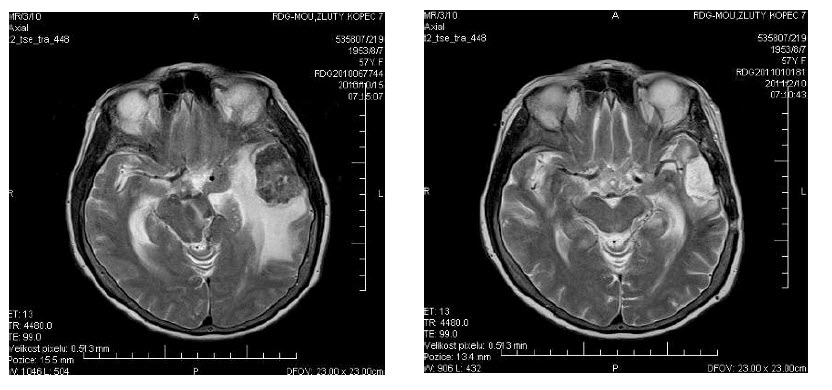

57letá pacientka s karcinomem ovaria v remisi po hysterektomii a bilaterální adnexetomii, po adjuvatní chemoterapii CBDCA/Taxotere byla v roce 2003 operována v Nemocnici Boskovice pro karcinom sigmatu. Provedena operace sec. Hartman s pooperačním stagingem pT3N0M0, histologicky přítomen adenokarcinom G2. V rámci adjuvatní terapie podána chemoterapie Xeloda v standardním režimu a provedeno adjuvatní ozáření malé pánve. Dále pacientka sledována. V 5/2007 dochází k progresi onemocnění, dle provedeného CT diagnostikována lokální recidiva + meta plic, laboratorně v korelaci dochází k elevaci tumor markerů (CEA, CA 19-9). Provedeno došetření KRAS, diagnostikován wt. Zahájena I. linie paliativní chemoterapie režimem FOLFOX + Avastin. Celkem aplikováno 15 sérií s efektem progrese nálezu na plicích a vzestupu tumorových markerů. Průběh komplikován vznikem enterovesikální a enterovaginální fistuly. Indikována reoperace se založením ter-minální sigmoideostomie na původním pracovišti. Pro současnou progresi po vyřešení zánětlivých komplikací zahájena II. linie paliativní chemoterapie režimem FOLFIRI. Dle přešetření po 4. sérií přítomna regrese nálezu na plicích, stacionární nález v malé pánvi, klinicky však nově motorický neklid, orální dyskineze, dle neurologického nálezu diferenciálně diagnosticky zvažovány NUL metoklopramidu, který vysazen a v plánu pokračováná terapie stávajícím režimem. Laboratorně však nově nárůst CEA a mírná progrese neurologické symptomatologie. Proto provedeno MRI mozku, kde nález objemné solitární expanze vlevo temporálně (45x40x40 mm) s výrazným kolaterálním edémem a přetlakem struktur střední čáry, diferenciálně diagnosticky na prvním místě metastáza. Zahájena antiedematosní terapie a konzultována neurochirurgická komise. V 10/2010 provedena exstirpace expanze, histologicky potvrzena metastatická diseminace karcinomu sigmatu. Pooperační radioterapie nebyla indikována. Po zákroku klinicky výrazná regrese neurologické symptomatologie, postupně téměř ad integrum, laboratorně výrazný pokles CEA (190,4...60,8...24,7...12,7). Vzhledem k normalizaci stavu pacientky - PS1, dosaženému efektu předchozí terapie rozhodnuto o pokračování stejným režimem. T. č. pacientka léčena 5. měsíc režimem FOLFIRI s výbornou tolerancí.